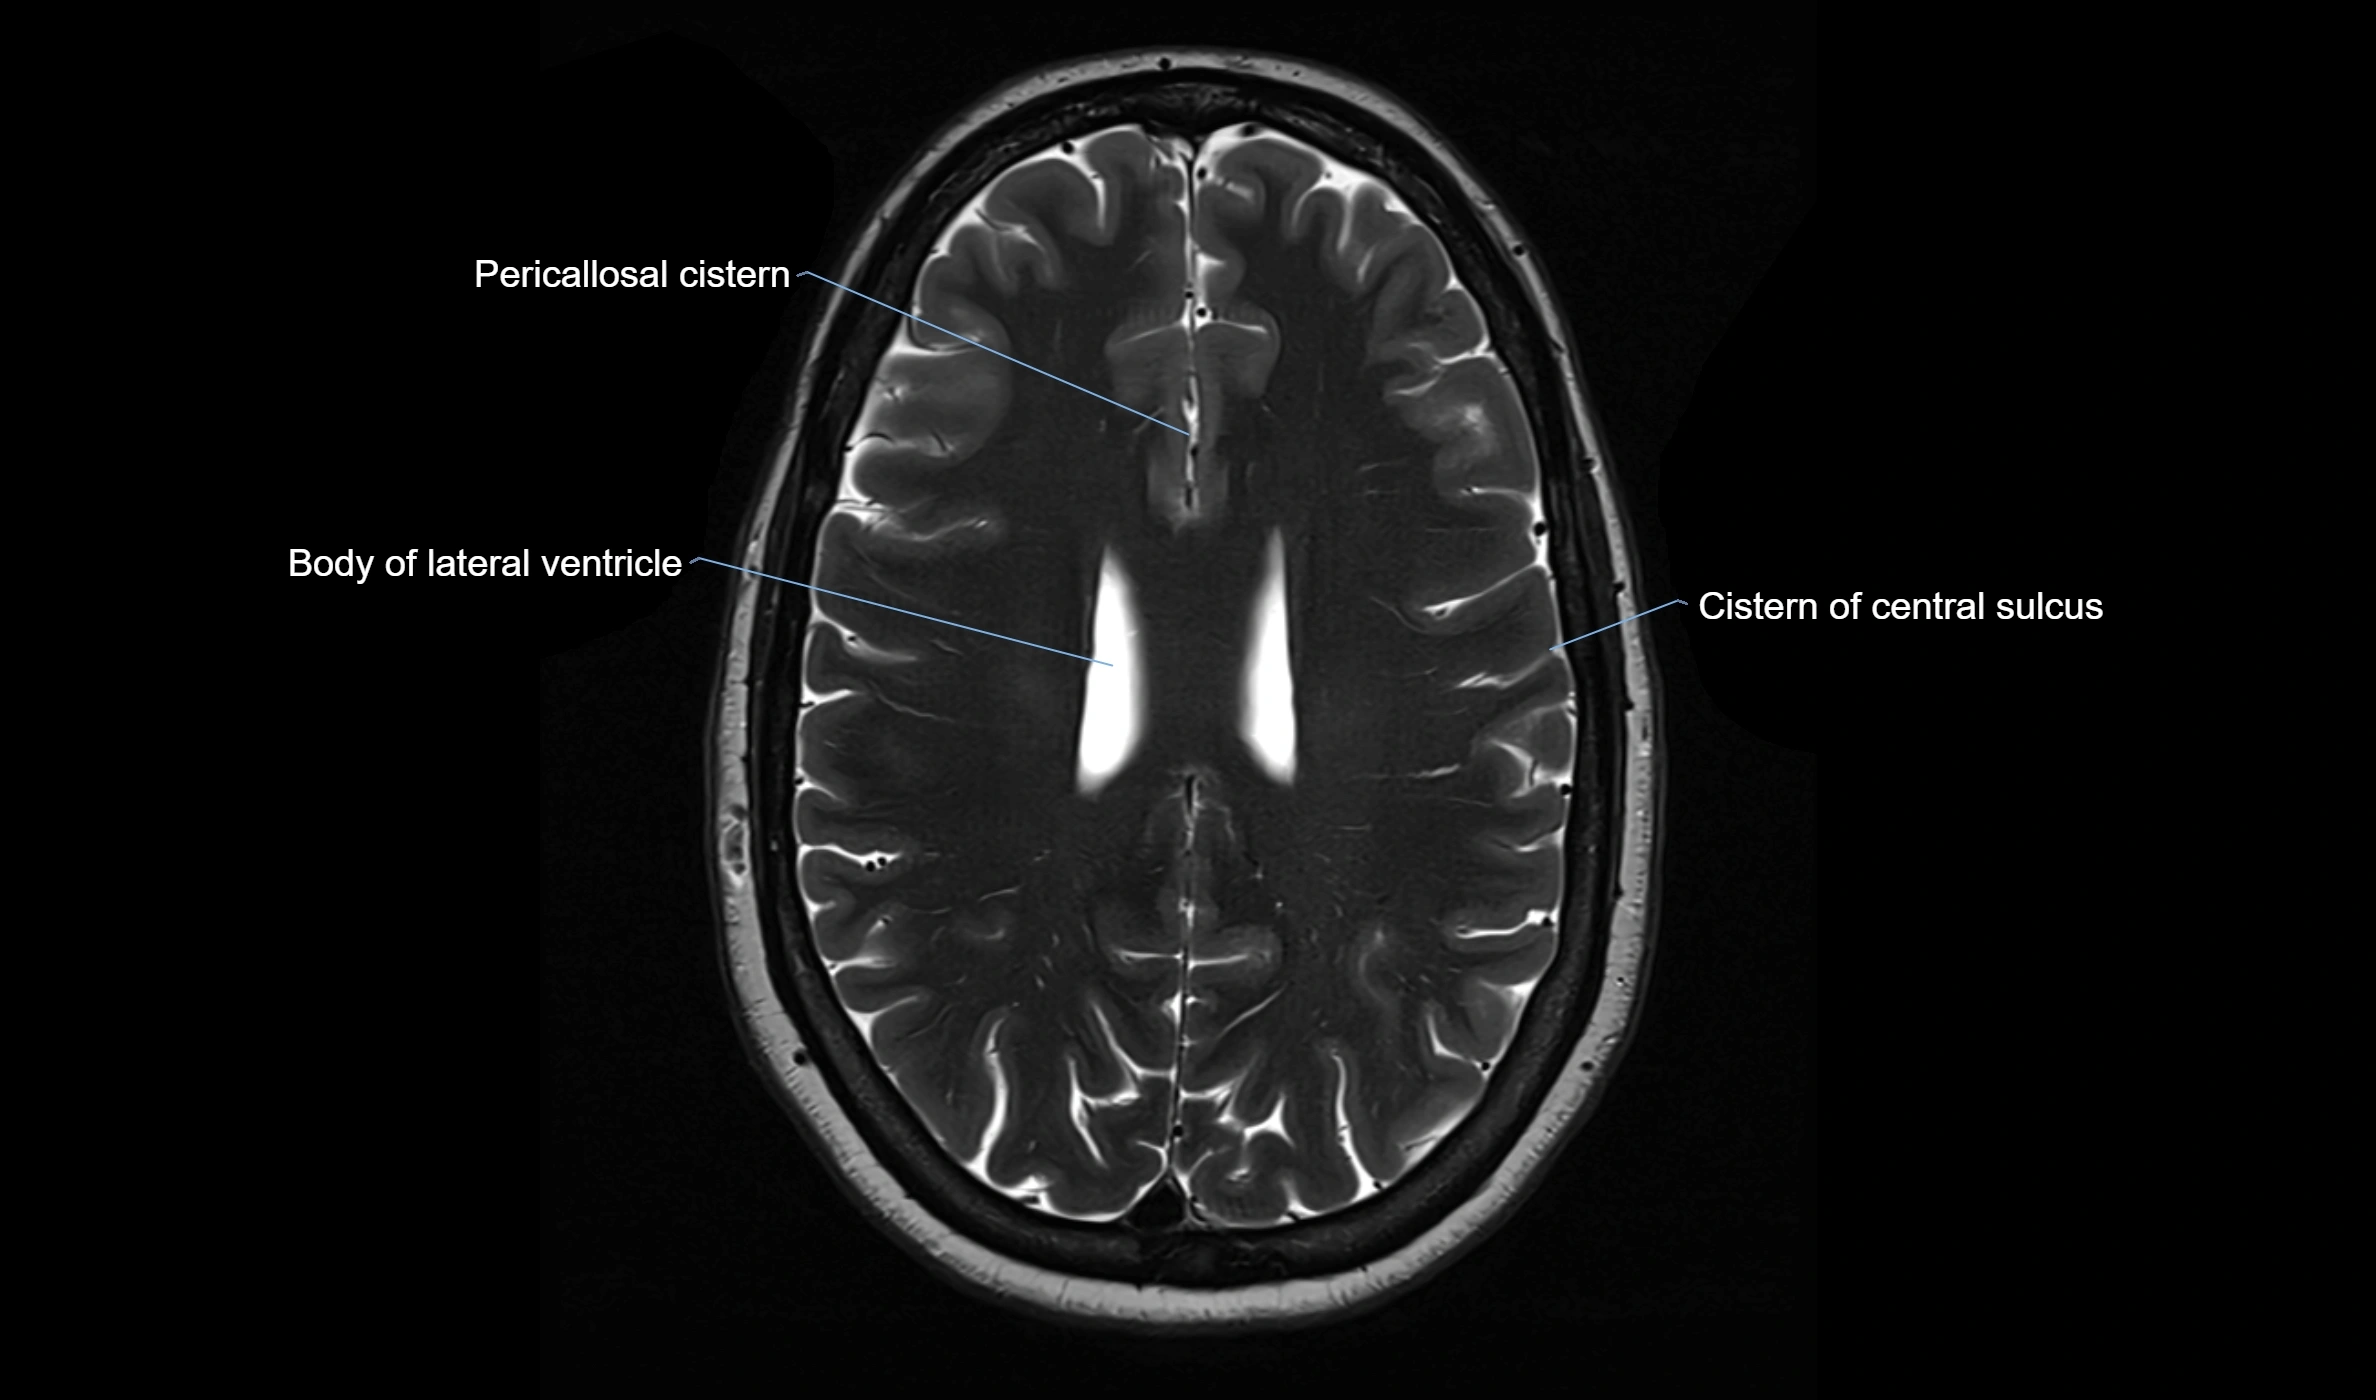

MRI images

image